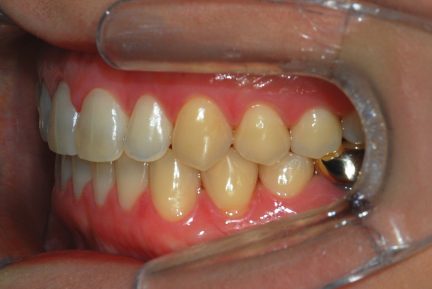

État final

- Relation de Classe I obtenue

- Guidage fonctionnel des canines des deux côtés

- Surplomb et recouvrement normaux obtenus

- Ligne esthétique du sourire obtenue

Surtout après la fermeture d'espace, le contrôle de l'inclinaison linguale buccale des dents antérieures inférieures était excellent.